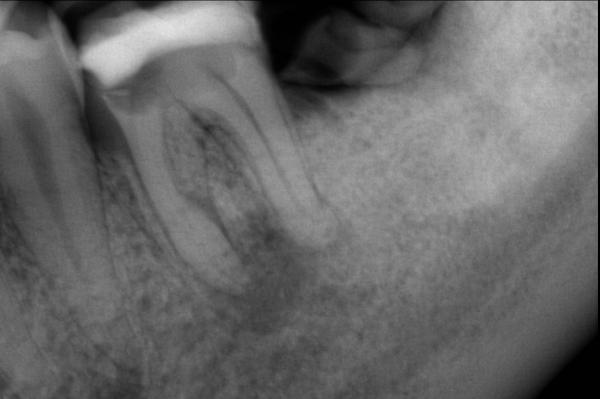

Endodoncia por caries en la raíz de la pieza dental

Paciente X de B años de edad, llega con amplia caries en la zona de a raíz. Se realiza endodoncia para salvarlo de una extracción. Al final se rehabilitó su pieza dental con una incrustación.

El paciente en su consulta de diagnóstico